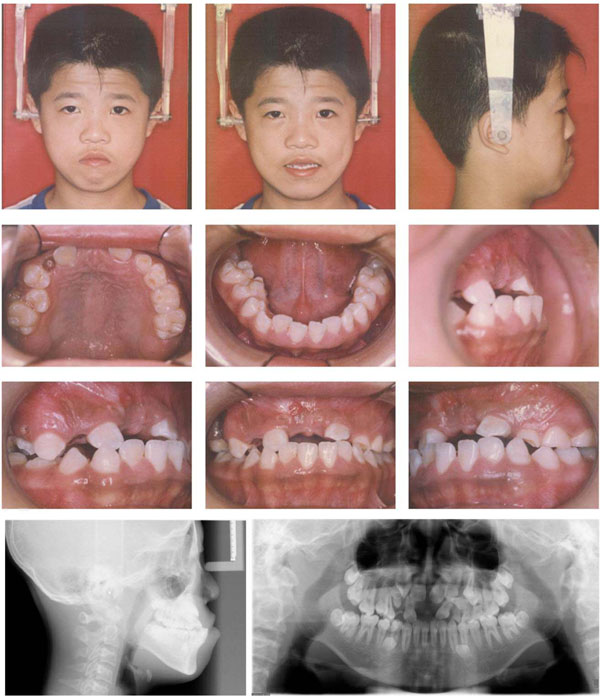

A 14-year-old boy was referred to our department for orthodontic consultation. His chief complaint was upper anterior teeth unerupted. His medical history indicated that he used to be weak during childhood and has drug induced deafness. He has normal stature and weight. Intelligence was subjectively normal. No signs of any genetic syndrome and metabolic disorders had been found. He has no reported dental traumatic history. No other family members were known to have similar abnormalities of the teeth and craniofacial skeleton. Clinical and radiographic examination revealed a skeletal Class III malocclusion. Extraorally, he had a relatively concave profile with underdevelopment of the maxilla and excessive mandibular growth. Intraorally, his upper posterior primary teeth in the left side were over-retained and maxillary central incisors, canines and left first premolars were impacted, together with several supernumerary teeth in both arches. Slight anterior crowding was noted in lower arch (Fig. 1). Cephalometric analysis indicated features of skeletal class III. The maxilla was retrusive (SNA = 75°), while the mandible was normal (SNB = 78°) in central occlusion, indicating a skeletal Class III (ANB = –3°). The mandible showed a forward and downward rotation and a hyperdivergent skeletal pattern (FMA=36°, SN-GoGn=39°). He denied ever having any temporomandibular joint (TMJ) dysfunction signs or symptoms, and maximal opening and lateral and anterior movements were within normal limits.

Pre-treatment facial, intraoral photos and radiographs.